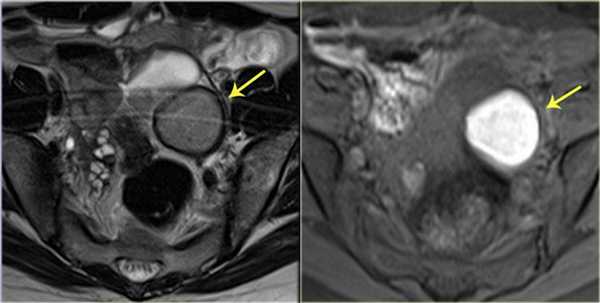

При МР-исследовании эндометриома представляет собой единичное образование (либо множественные образования) с однородным гиперинтенсивным сигналом на Т1 взвешенных томограммах и при использовании последовательностей Т1 с жироподавлением, которые помогают в дифференциальной диагностике эндометриом и зрелых кистозных тератом, обычно содержащих жировую ткань. На Т2 ВИ эндометриомы могут давать гипоинтенсивный сигнал (в виде «слабой тени»), а также промежуточный или гиперинтенсивный сигнал. Характеристики сигнала отражают содержание крови в кисте. Эндометриомы обычно имеют толстую капсулу из фиброзной ткани с низкой интенсивностью сигнала на Т2, обусловленную макрофагами, заполненными гемосидерином.

МРТ-признаки эндометриоидной кисты. На Т2 взвешенной и Т1 взвешенной МР-томограммах с жироподавлением визуализируется эндометриома, дающая гипоинтенсивный сигнал на Т2 («слабая тень») с уровнями «жидкость-жидкость» (слева), и гиперинтенсивным сигналом на Т1 с жироподавлением (справа)

На МР-томограммах, выполненных пациентке с эндометриомой правого яичника (желтая стрелка) образование дает промежуточный по интенсивности сигнал на Т2 ВИ и гиперинтенсивный на Т1 ВИ с жироподавлением. Дополнительно видны признаки гидросальпинкса с высокой интенсивностью сигнала на Т2 ВИ и гипоинтенсивным сигналом на Т1 с жироподавлением (красная стрелка), а также лейомиома матки, гипоинтенсивная на Т2 ВИ и с промежуточным по интенсивности сигналом на Т1 с жироподавлением (голубая стрелка)